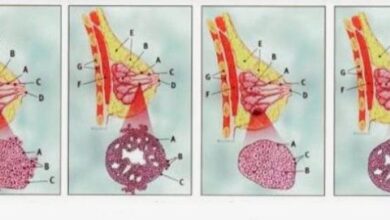

يوجد ثلاث طرق لفحص الثدي للتشخيص المبكر لمرض سرطان الثدي:

- الفحص الذاتيّ: تقوم السيدة بالفحص الذاتي للثدي في المنزل ويُفضّل أن تقوم به أثناء الاستحمام حيث إنّ رغوة الصابون تساعد في سهولة الفحص الذاتي، ويفضّل عمل الفحص الذاتي للثدي بعد انتهاء الدورة الشهريّة، ويفضّل أن تقوم السيدات بالفحص الذاتيّ مرّة كلّ شهر، مثلاً إذا أرادت السيدة فحص الثدي الأيسر، ترفع ذراعها الأيسر فوق رأسها وباستخدام أصابع اليد اليمنى تبدأ بحسّ الثدي بشكل دائريّ وتحت الإبط، وملاحظة شكل الحلمة ولون جلد الثدي وملاحظة أيّة تغيرات في طبيعة جلد الثدي، فعلى كلّ سيدة أن تعرف قوام الثدي عندها وفي حال ملاحظة أيّة تغيرات أو حسّ أيّ كتلة يجب التوجّه إلى الطبيب فوراً والقيام بفحص الأشعة الماموغرام.

يجدر بالسيدة التوجه إلى الطبيب مباشرة في حالة لاحظت أي من هذه الحلات أثناء الفحص.

- في حال حس وجود كتلة في الثدي حتى لو لم يكن هناك ألم.

- ملاحظة وجود تغير في لون جلد الثدي أو تغير شكل الحلمة وتغير في طبيعة الجلد في الثدي حيث أنه في حال وجود الأورام الخبيثة المتقدمة يتغير شكل جلد الثدي ليصبح له قوام قشرة البرتقالة.

- خروج إفرازات من الحلمة سواء كانت هذه الإفرازات عبارة عن دم أو إفرازات صفراء اللّون أو الاثنين معاً.

- ملاحظة وجود تورّم أو انتفاخ في الغدد اللّمفاوية تحت الإبط.